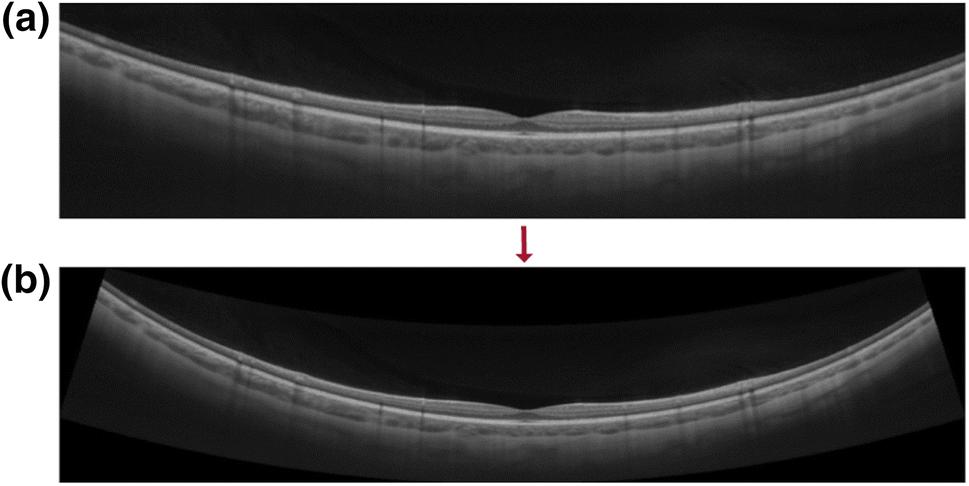

Figure 3

(a) Uncorrected, “original” OCT B-Scan of 16 mm length in 80\(^\circ\) scan orientation. (b) Output B-scan after distortion-correction. Note the increased curvature compared to the artificially flattened, original scan image in (a).